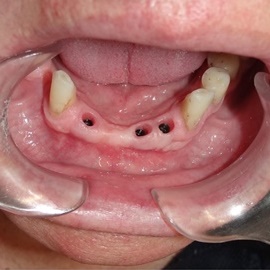

• Implanty jako zakotwiczenie protezy częściowej i całkowitej

Nie u każdego pacjenta można wykonać stałe odbudowy protetyczne oparte na implantach. Powody najczęściej sa prozaiczne, takie jak koszty, niekorzystne początkowe warunki kostne i wymagane rozległe odbudowy kości, strach przed bólem a także - jakże często - zdrowy rozsądek. Wiadomo bowiem, że w przypadku rozległych, trudnych technicznie do wykonania regeneracji kostnych zwiększa się obciążenie organizmu, oraz możliwości wystąpienia powikłań, a więc zwiększa się ryzyko niepowodzenia w leczeniu. Dlatego wykorzystujemy implanty jako zakotwiczenie atachmentów do utrzymania protezy ruchomej. Takie rozwiązanie pozwala na zmniejszenie kosztów, ograniczenie zakresu zabiegu, oraz co najważniejsze pozwala na poprawę jakości życia i zadowolenia z użytkowania protez ruchomych.

Pacjentka głosiła sie do naszego gabinetu do leczenia z osadzonym mikroimplantem w pozycji lewej dolnej dwójki. Siostrzany implant w pozycji prawej dolnej dwójki wypadł wcześniej, około 1,5 roku od implantacji. Odtworzono przedsionek i dziąsło rogowaciejące, osadzono dwa implanty, jednoczasowo z regeneracją kości. Dopiero na etapie ostatecznej rekonstrukcji protetycznej usunięto zachowany mikroimplant. To się nazywa motywacja do leczenia! Pacjentka przygotowywała sie na ślub prawnuczki :)